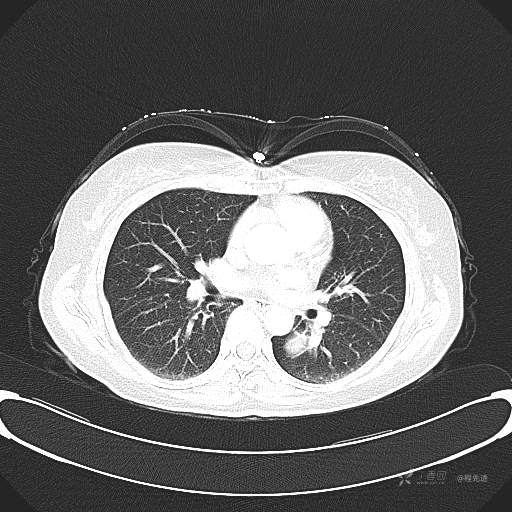

6月特别精彩病例|中老年女性,体检发现左肺下叶肿块,期待你的精彩演绎【病理公布】

患者性别:女

患者年龄:57岁

简要病史:体检发现

CT增强

平扫CT值约40HU(未上传图像),增强后动脉期CT值约70HU,静脉期CT值约97HU。

肺硬化性血管瘤 (20)